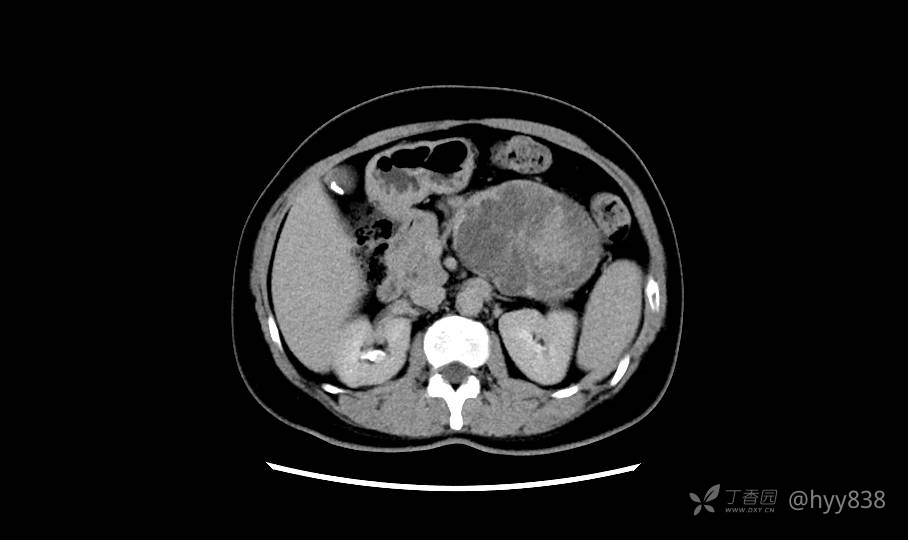

静脉期(机器故障---延迟期了)